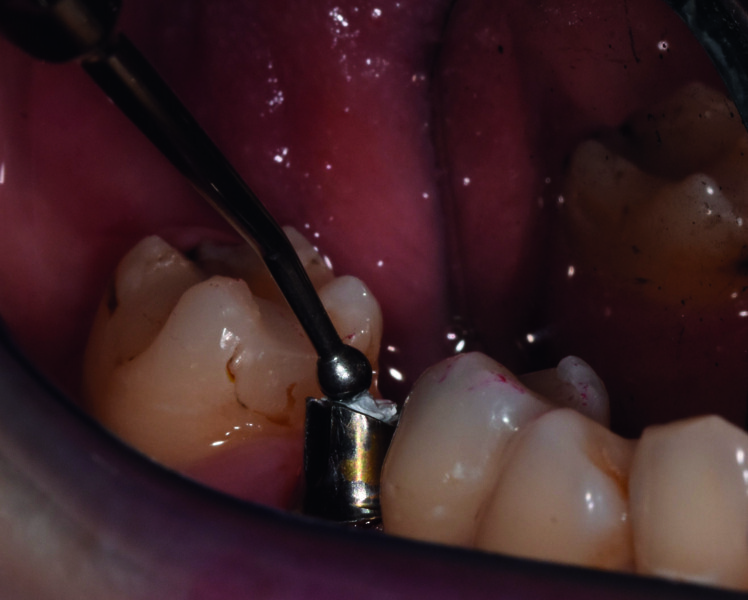

Pour la technique scellée on utilise un piler à base concave pour une meilleure étanchéité de la gencive. On remplit le puit du pilier avec du téflon, que l’on tasse et foule avec l’instrument de chez PRODONT-HOLLINGER/ACTEON réf. 206.10D (Fig. 22).

Fig. 22 : Fouloir cylindrique d’un côté et fouloir boule de l’autre.

Fig. 23 : Teflon mis dans le fût du pilier.

Fig. 24 : D’un côté fouloir cylindre pour remplir le fût avec le téflon.

Fig. 25 : De l’autre côté : fouloir boule pour tasser le téflon.